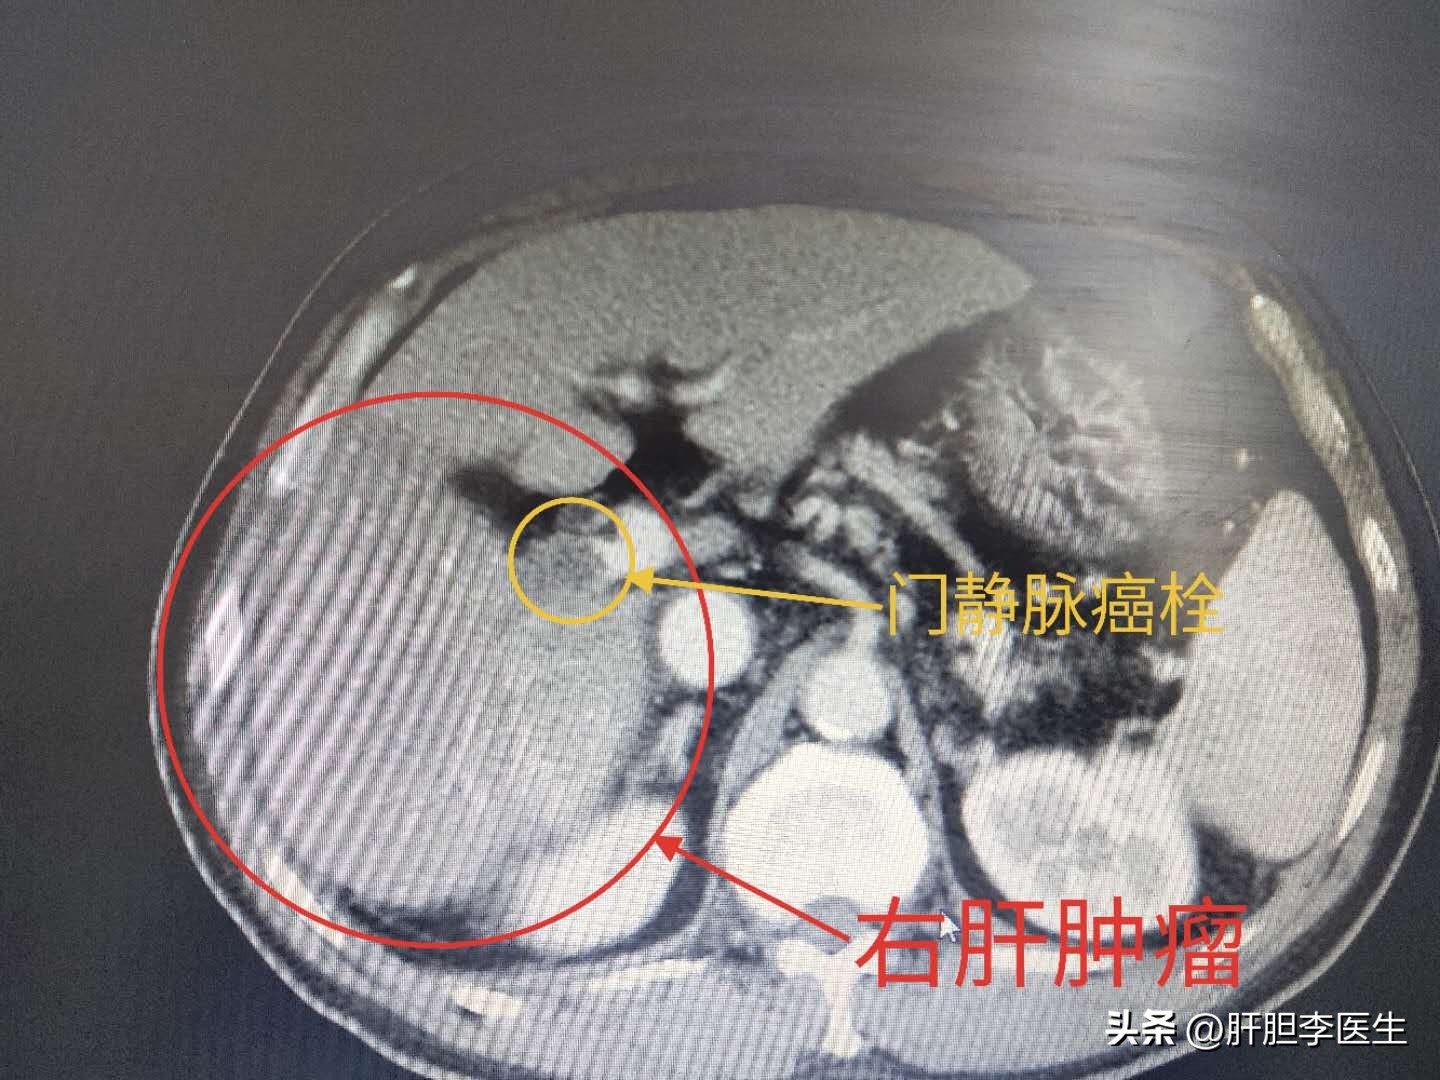

虽然后来经过抢救病情稳定了,但是由于肿瘤比较大,而且已经出现了门静脉癌栓,已经是肝癌晚期了,后面也只能继续做介入+靶向治疗来尽量控制肿瘤的发展,延长生存时间了。